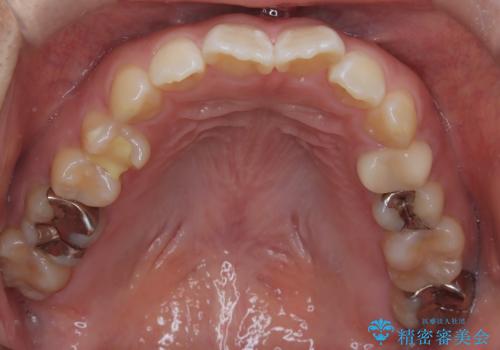

- 口元が出ている(突出している)ことを気にされて来院されました。精密な検査の結果、前歯を大きく後退させるスペースが必要と診断。患者様の**「前歯を下げたい」という強いご要望に応えるため、上下左右の第一小臼歯を抜歯し、そのスペースを利用して前歯を奥へ移動させる治療計画を立案しました。また、人目を気にせず治療できるよう、上顎に裏側矯正、下顎に表側矯正を組み合わせたハーフリンガル矯正**を提案しました。

今回の矯正治療では、前歯を大きく後退させるスペースを確保するため、計画通り上下左右の第一小臼歯を抜歯しました。装置には、上顎には目立たない裏側矯正(舌側矯正)を、下顎には透明な審美ブラケットを使用するハーフリンガル矯正を採用しました。抜歯によってできたスペースを最大限に活用し、前歯を効率よく後方へ移動。治療の結果、口元の突出感が大幅に解消され、Eライン(横顔の美しさの基準)も改善しました。人目を気にすることなく治療を完遂し、自信の持てる美しい横顔を獲得していただけました。